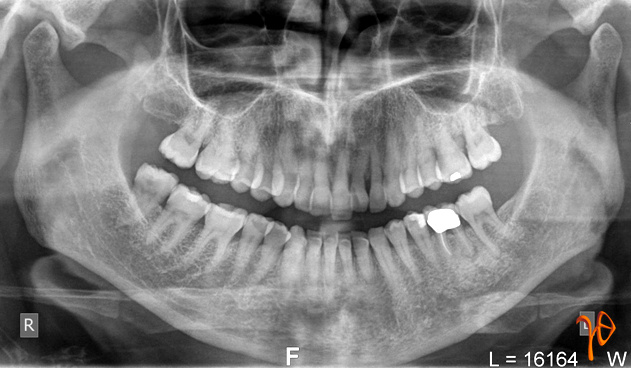

Τα δόντια στην περιοχή ήταν ζωντανά και η πανοραμική ακτινογραφία(Εικόνα 2) δεν έδειξε σημαντικά ευρήματα στο οστούν της άνω γνάθου της εξεταζόμενης περιοχής.

Εικόνα 2. Πανοραμική ακτινογραφία